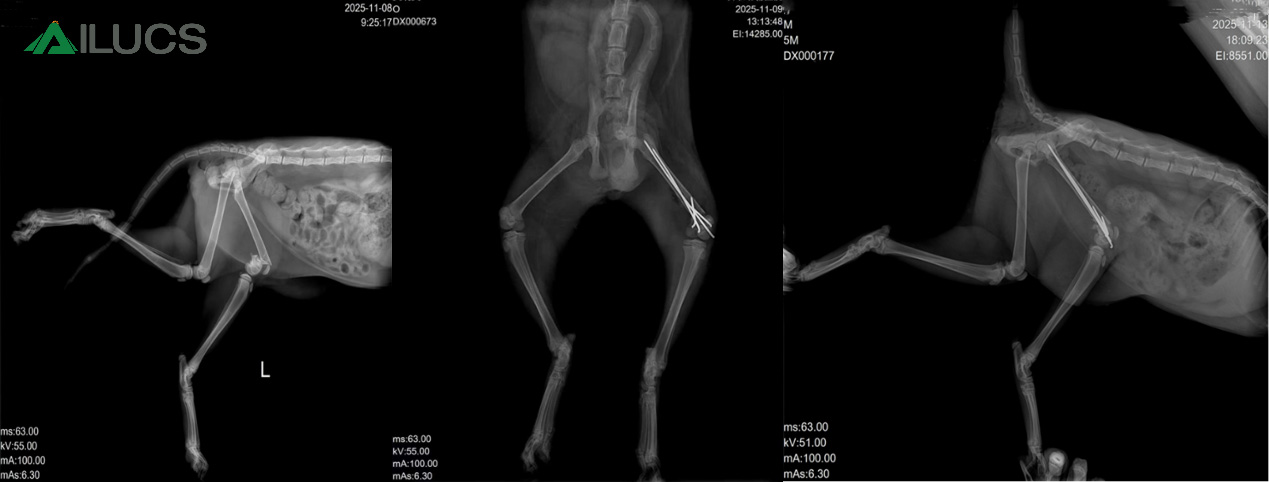

Recently, we witnessed the remarkable recovery of a three-month-old kitten named Oreo, who suffered a severe fracture but regained mobility quickly and significantly with the help of the Lyra Laser Therapy device. This case not only showcases the tremendous potential of laser therapy in veterinary medicine, but also provides pet owners with a scientific and effective new approach to fracture care.

Oreo sadly experienced a serious accident that resulted in a severe fracture with noticeable bone fragmentation and misalignment. Faced with such an acute injury, traditional surgery became the preferred treatment option. The surgery was successful, and the bones were realigned, but the veterinarian pointed out that small gaps remained at the fracture site. To ensure proper healing, additional rehabilitation therapy was needed.

In Oreo’s case, Lyra veterinary laser treatment began 24 hours after surgery. Remarkably, after just one session, the kitten was able to stand on her own. One more day of therapy later, Oreo was already able to walk—though with a slight limp. This rapid improvement strongly demonstrates the significant role laser therapy can play in fracture recovery.